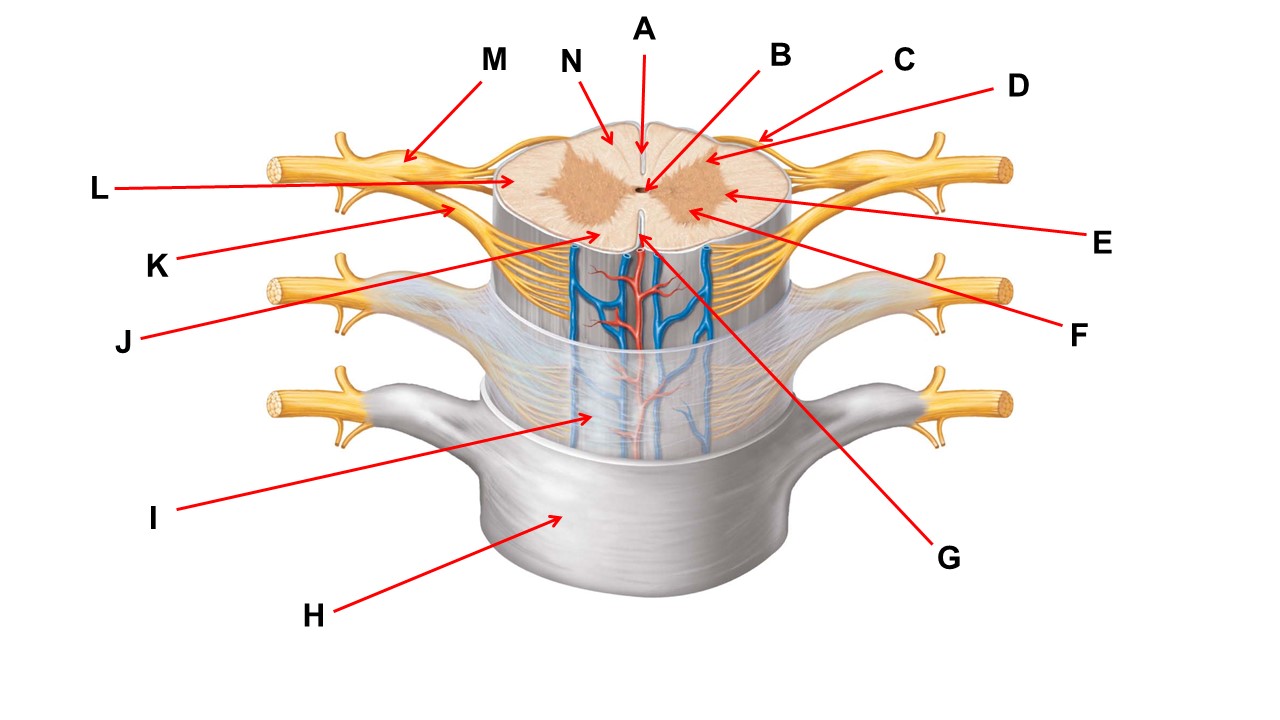

Name the region within bracket D.

Name the region of tissue surrounding the tip of arrow E.

Name the region of tissue surrounding the tip of arrow B.

Name the structure at the tip of arrow K.

ventral root

Name the region of tissue surrounding the tip of arrow J.

Name the layer at the tip of arrow I.

Name the region of tissue surrounding the tip of arrow E.

Name the region of tissue surrounding the tip of arrow N.

Name the deep groove at the tip of arrow G.

Which structure(s ) would be found in the area at the tip of arrow D.

Name the region of tissue surrounding the tip of arrow E.

Name the region within bracket G.